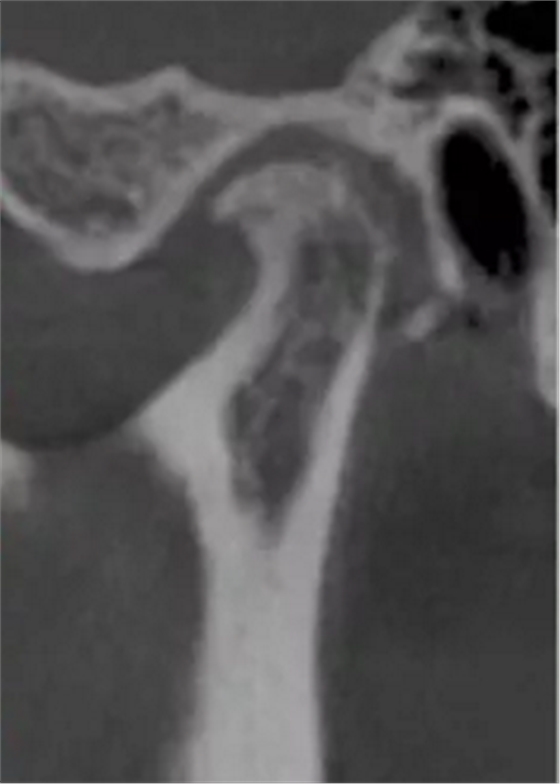

更嚴(yán)重的是會影響下頜關(guān)節(jié)的健康,正常下頜運(yùn)動三模式開口運(yùn)動,側(cè)方咬合,前伸下頜,閉鎖合時只留開口運(yùn)動模式了,其他二種只有先開口后才能發(fā)生。這樣由于上前牙內(nèi)傾,強(qiáng)迫下頜后退,使下頜關(guān)節(jié)位置異常,關(guān)節(jié)頭越磨越平。這類人群往往有關(guān)節(jié)區(qū)疼痛、張閉口彈響,張不開口等,嚴(yán)重的會影響日常生活和情緒。

關(guān)節(jié)頭損傷